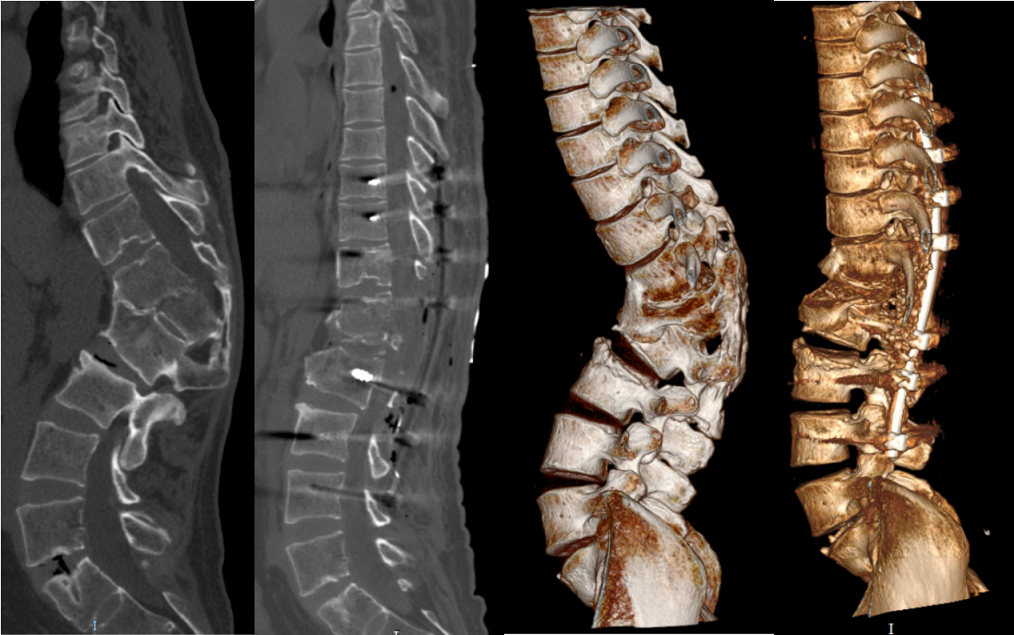

病例分享:脊柱后凸畸形矫形术

图片尺寸1376x641